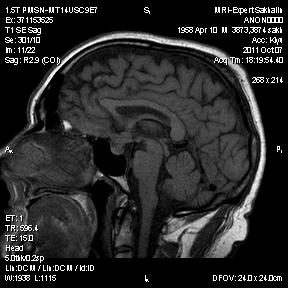

Аденома гипофиза

Вот такая аденома гипофиза сегодня.Мужчина с жалобами на снижение зрения.

Публикации: 175

Мне кажется что это все же не аденома, может глиома хиазмы ? (воронки гипофиза)? Или еще какое-нибудь объемное образование.... Что то меня смущает, еще не поняла что, но В любом случае наверное я бы однозначно не писала что это аденома, а выставила бы весь диф. ряд.

Танюша, обычно пишем "образование хиазмально-селлярной области"

Присоединяюсь к последнему коментарию, все таки откуда растет по моему мнению трудно однозначно сказать, лучше себя обезопасить написав "объемное образование хиазмально-селлярной области"